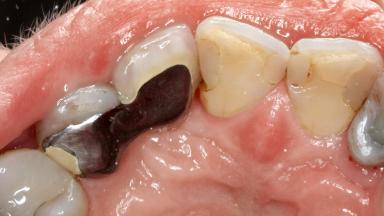

Surgical Management of Peri-Implantitis: Removal of Implant Due to Recurrent Infection Using an Implant-Retrieval Tool

Despite anti-infective surgical treatment, some patients may experience recurrent infection and progressive bone loss requiring additional treatment. This case describes a conservative approach using an implant retrieval tool without the need for excessive bone removal or use of a trephine.

A 65-year-old female patient was referred to the periodontist for assessment and management of infection associated with an implant at site 12. The general dentist had noted suppuration on probing during examination.